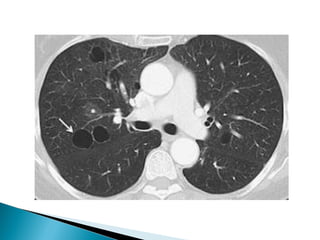

 Def= vizualizarea calibrului crescut si contrastarii intense a

vaselor pulmonare intr-o condensare pulmonara vizualizata in

,,fereastra de mediastin’’

 Etiologii: cancer bronhoalveolar

limfom

pneumonie infectioasa si postobstructiva

edem pulmonar

mts date de cancere gastrointestinale

 Fig. 5 semnul

angiogramei CT;

pacient cu cancer

bronhoalveolar

(contrastarea

vasculara intr-o masa

tumorala)